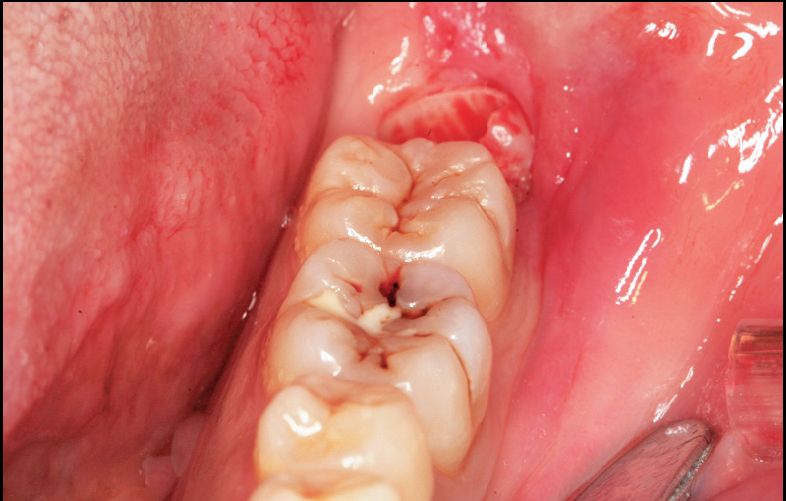

根部阻力较大者的智齿形态

根部阻力较小的智齿形态

单根牙、根分叉不大者、合并根、融合根、特短根、锥形根阻力较小。若根尖区向远中弯曲、无弯曲或根尖未形成,则阻力也较小。